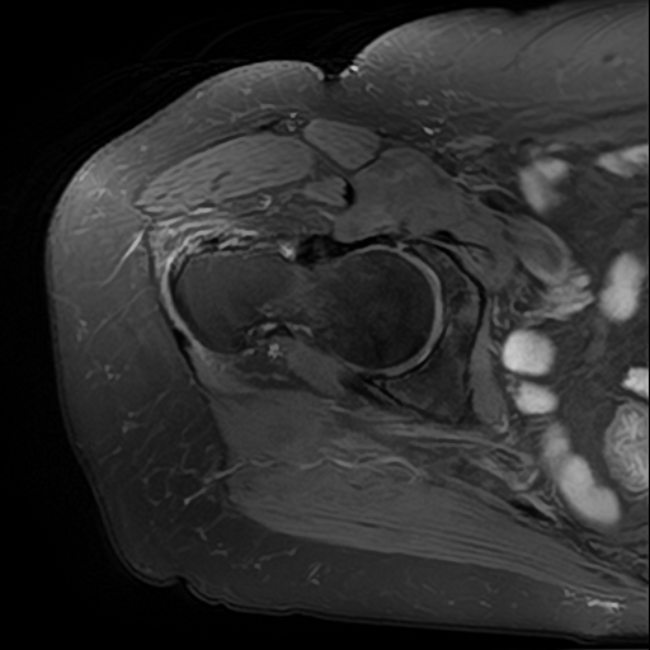

Davant la sospita de lesió dels tendons de la musculatura glutea es decideix demanar un RM del maluc que confirma l'arrencament d'aquests tendons a nivell de la seva inserció al trocanter.